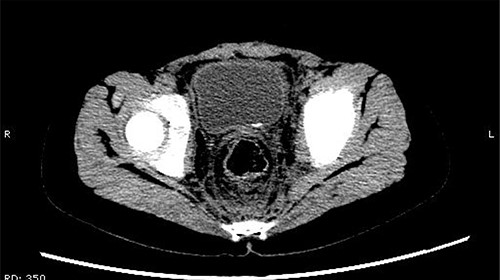

On 25 February, the patient complained of left back pain, nausea and vomiting. A further CT scan showed some irregular high-density shadows persisted in the left renal pelvis (Fig. 3) and an irregular high-density shadow was present in the left upper ureter (Fig. 4); furthermore, hydronephrosis was apparent in the left renal pelvis. There were no abnormalities in the bladder.

Some irregular high-density shadows persisted in the left renal pelvis, hydronephrosis was apparent in the left renal pelvis.